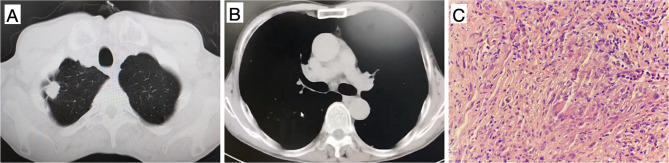

Case presentation: A 66-year-old male visited a local hospital with symptoms such as cough and hemoptysis. A computed tomography (CT) scan of the chest revealed a mass in his right lung, and no mediastinal lymphadenopathy was observed. Bronchoscopy showed no major abnormalities, and the results of fine needle aspiration biopsy showed granulomatous inflammation. Even though the patient received anti-infection treatment, his symptoms did not improve markedly. After two months, a follow-up CT scan of the lung showed a noticeably enlarged mass accompanied by multiple instances of mediastinal lymphadenopathy in the upper lobe of the right lung. Consequently, he underwent a second CT-guided lung biopsy at our hospital. The pathology report indicated PSCC. Due to financial constraints, genetic testing was not performed. Given his poor overall physical condition, the patient was unable to undergo systemic chemotherapy and instead received palliative radiotherapy. The prescribed radiotherapy dose for the right upper lobe lung cancer and multiple metastatic lymph nodes was 60 Gy, administered in 30 fractions. Unfortunately, he failed to adhere to scheduled follow-ups and succumbed to the disease 6 months later, as confirmed during a telephone follow-up.